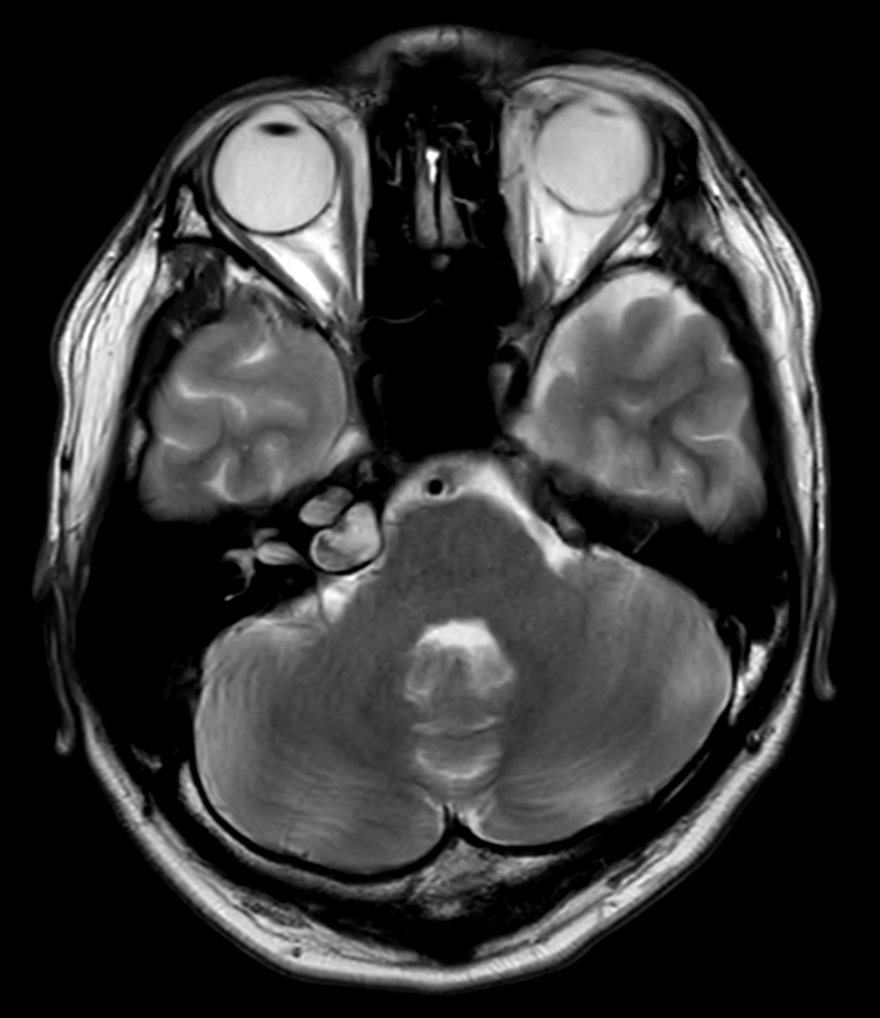

Patient with an IAC lesion. Comparing different DWI methods (EPI, TSE, ZOOM). Compressed SENSE is added to all TSE sequences to decrease scan times, thereby shortening the time the patient has to spent in the magnet. The dS Head 32ch coil is used to enhance image quality.

T2w TSE